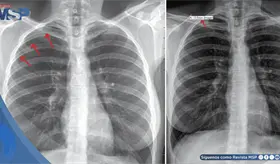

El intenso dolor torácico no fue una recaída ni metástasis, sino un daño óseo provocado por la reirradiación. Los huesos, debilitados por la radioterapia previa y la reirradiación, estaban perdiendo su capacidad de curarse adecuadamente.